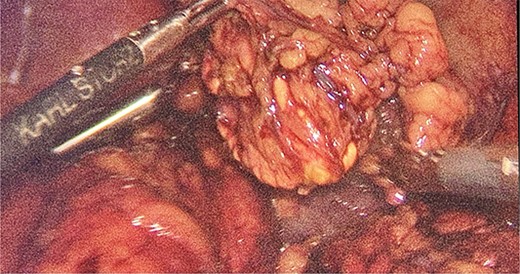

We had to first liberate the adhesions of the colon from a previous operation before gaining entry to the left colon. To do so, we made an incision in the White line of Toldt and dissected the right gastrocolic and splenocholic ligaments. This allowed us to access the retrocolic space and approach the left kidney. We identified the left renal vein and the left suprarenal gland and dissected the gland from the fatty tissue of the kidney. The gastrosplenic ligament was also liberated through the ligation of short gastric arteries. After separating the stomach from the posterior abdominal wall, we located the GIST (Fig. 3) on the posterior part of the fundus and removed it through wedge resection (Fig. 4).